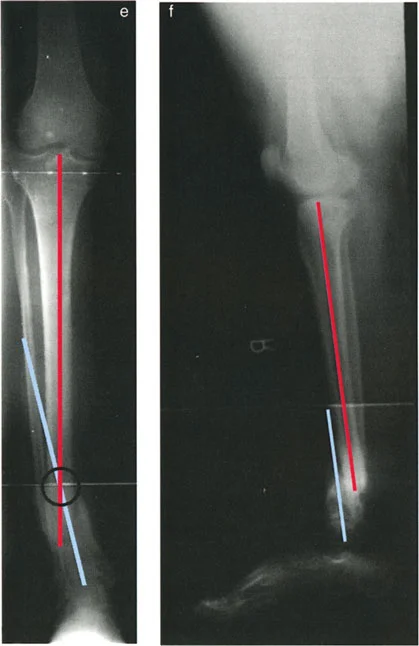

تشوهات المستوى المائل بزاوية أقل من 90 درجة

هذا هو النوع الأكثر تعقيدًا، حيث يظهر كل من الانحراف والانزياح في كل من الأشعة السينية الأمامية الخلفية (AP) والجانبية (LAT)، تمامًا كما في النوع الثاني (المستوى المائل بزاوية 90 درجة). ومع ذلك، عندما تُحدد مستويات جميع مكونات التشوه، تكون مختلفة عن بعضها البعض ولكن بزاوية أقل من 90 درجة.

مثل النوع الثاني، تكون مراكز دوران الانحراف (CORAs) على الأشعة السينية الأمامية والخلفية (AP) والجانبية (LAT) في مستويات مختلفة (أحدهما قريب والآخر بعيد عن مستوى الكسر). لأن كلا التشوهين يقعان في مستوى مائل والزاوية بين المستويين أقل من 90 درجة، قد نحتاج إلى أربع صور أشعة سينية مائلة مختلفة لإظهار أقصى وأدنى مكونات الانحراف والانزياح.

الميزة الرئيسية هنا هي أنه لا يوجد مستوى إسقاط شعاعي لا يظهر فيه وجود إما انحراف أو انزياح. أي أنك لن تجد مستوى يظهر فيه الانحراف فقط بدون انزياح، أو الانزياح فقط بدون انحراف، لأن المستويين ليسا متعامدين تمامًا.

مثال: انحراف وانزياح في مستويين مائلين مختلفين بزاوية أقل من 90 درجة. يظهر الانحراف والانزياح في كل من الأشعة السينية الأمامية والخلفية (AP) والجانبية (LAT).

إذا ظهر بعض الانزياح في كلا الأشعتين المائلتين، فهذا يعني أن مستوى الانزياح لا يمكن أن يكون متعامدًا (90 درجة) مع مستوى الانحراف.